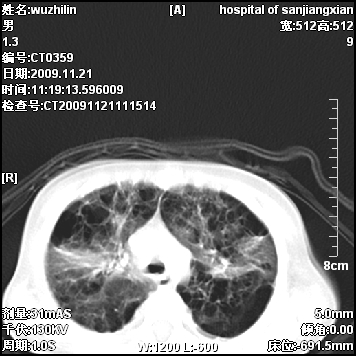

标题: PED3072: 1岁3个月患儿 胸部弥漫性病变 [打印本页]

标题: PED3072: 1岁3个月患儿 胸部弥漫性病变

弥漫性薄壁囊腔,胸膜下及肺底部占优势,双上肺磨玻璃密度影,首先考虑特发性肺间质纤维化,其次囊性肺纤维化,肺淋巴管平滑肌瘤病嗜酸性肉芽肿等;要结合临床综合考虑。

两肺布满多个薄壁含气囊腔,以下肺居多,伴磨玻璃样密度影,左侧气胸。两肺发育不全、两肺多发肺囊肿并感染,其次考虑肺囊腺瘤。